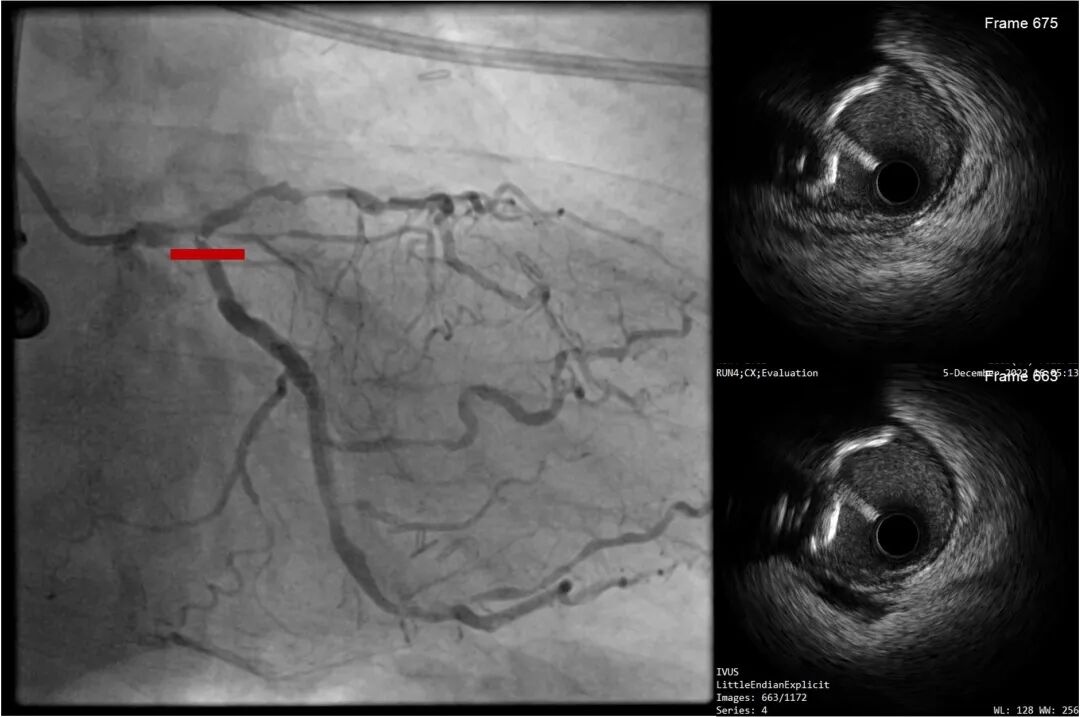

LAD近段-LM IVUS提示为270°环形钙化

LAD近段-LM 选择shockwave4.0*12mm,间断触发脉冲,每5个脉冲为一组,只4atm治疗,防止患者缺血省略6atm扩张,每次回撤Guiding,使用5个周期;

复查LAD近段-LM IVUS,钙化环明显断裂